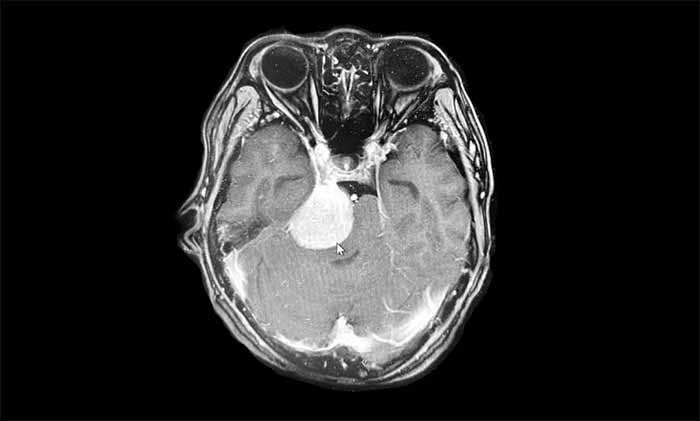

▲ 右侧桥小脑角-岩斜区脑膜瘤

患者因“头晕、乏力伴耳鸣四月余”就诊,检查发现肿瘤大小约4cm。更棘手的是,患者长期服用活血补品,导致肿瘤血供异常丰富,增加了手术难度。

在周范民教授的指导下,卢云鹤博士团队制定了周密详尽的手术方案。术中采用显微镜下精细操作,顺利切除肿瘤,保护了脑干和重要神经结构。术后患者恢复良好,原有症状缓解,无其他新发神经功能缺损。